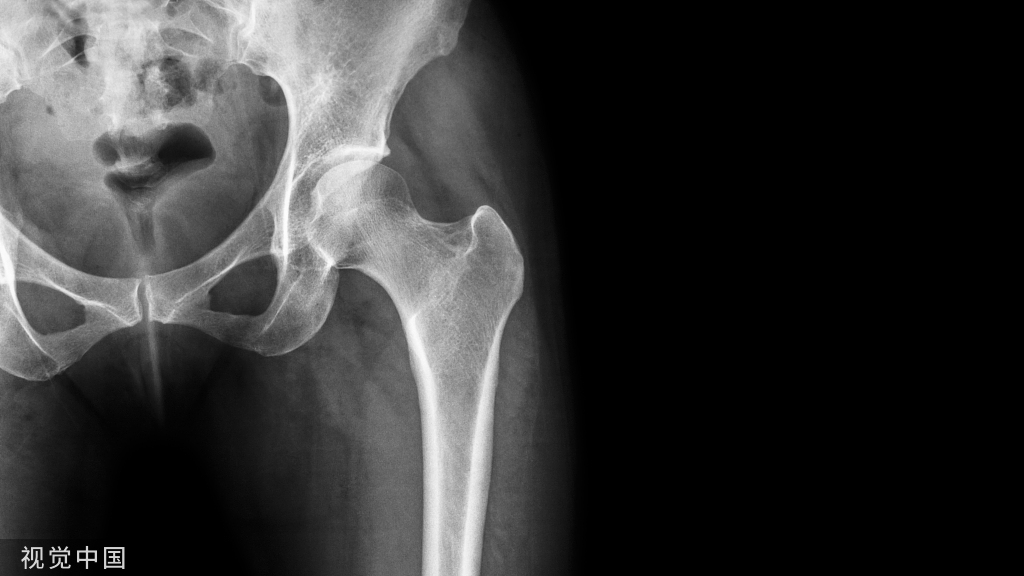

髋臼骨折由高能量损伤所致,多见于青壮年,骨折块移位可导致髋关节匹配丧失,若不经复位而任其畸形愈合,将导致股骨头与髋臼接触面减小,局部压力增加,引起关节软骨塌陷,最终导致创伤性关节炎。

髋臼骨折由高能量损伤所致,多见于青壮年,骨折块移位可导致髋关节匹配丧失,若不经复位而任其畸形愈合,将导致股骨头与髋臼接触面减小,局部压力增加,引起关节软骨塌陷,最终导致创伤性关节炎。髋臼骨折手术治疗需恢复髋臼形态、接触区几何形态和关节内压力分布